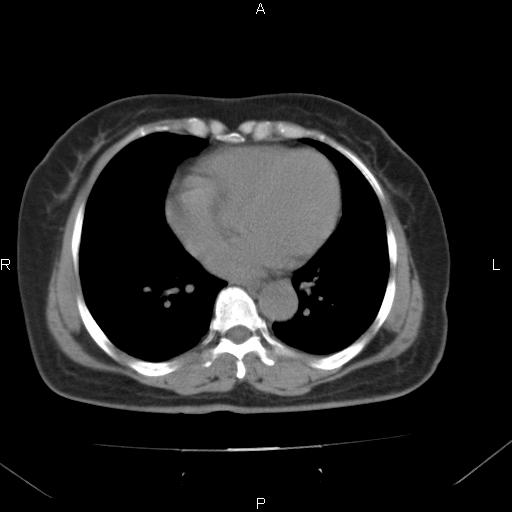

胸腺瘤

女、63Y 双眼睑下垂,早轻晚重。 胸腺瘤???

结果胸腺瘤